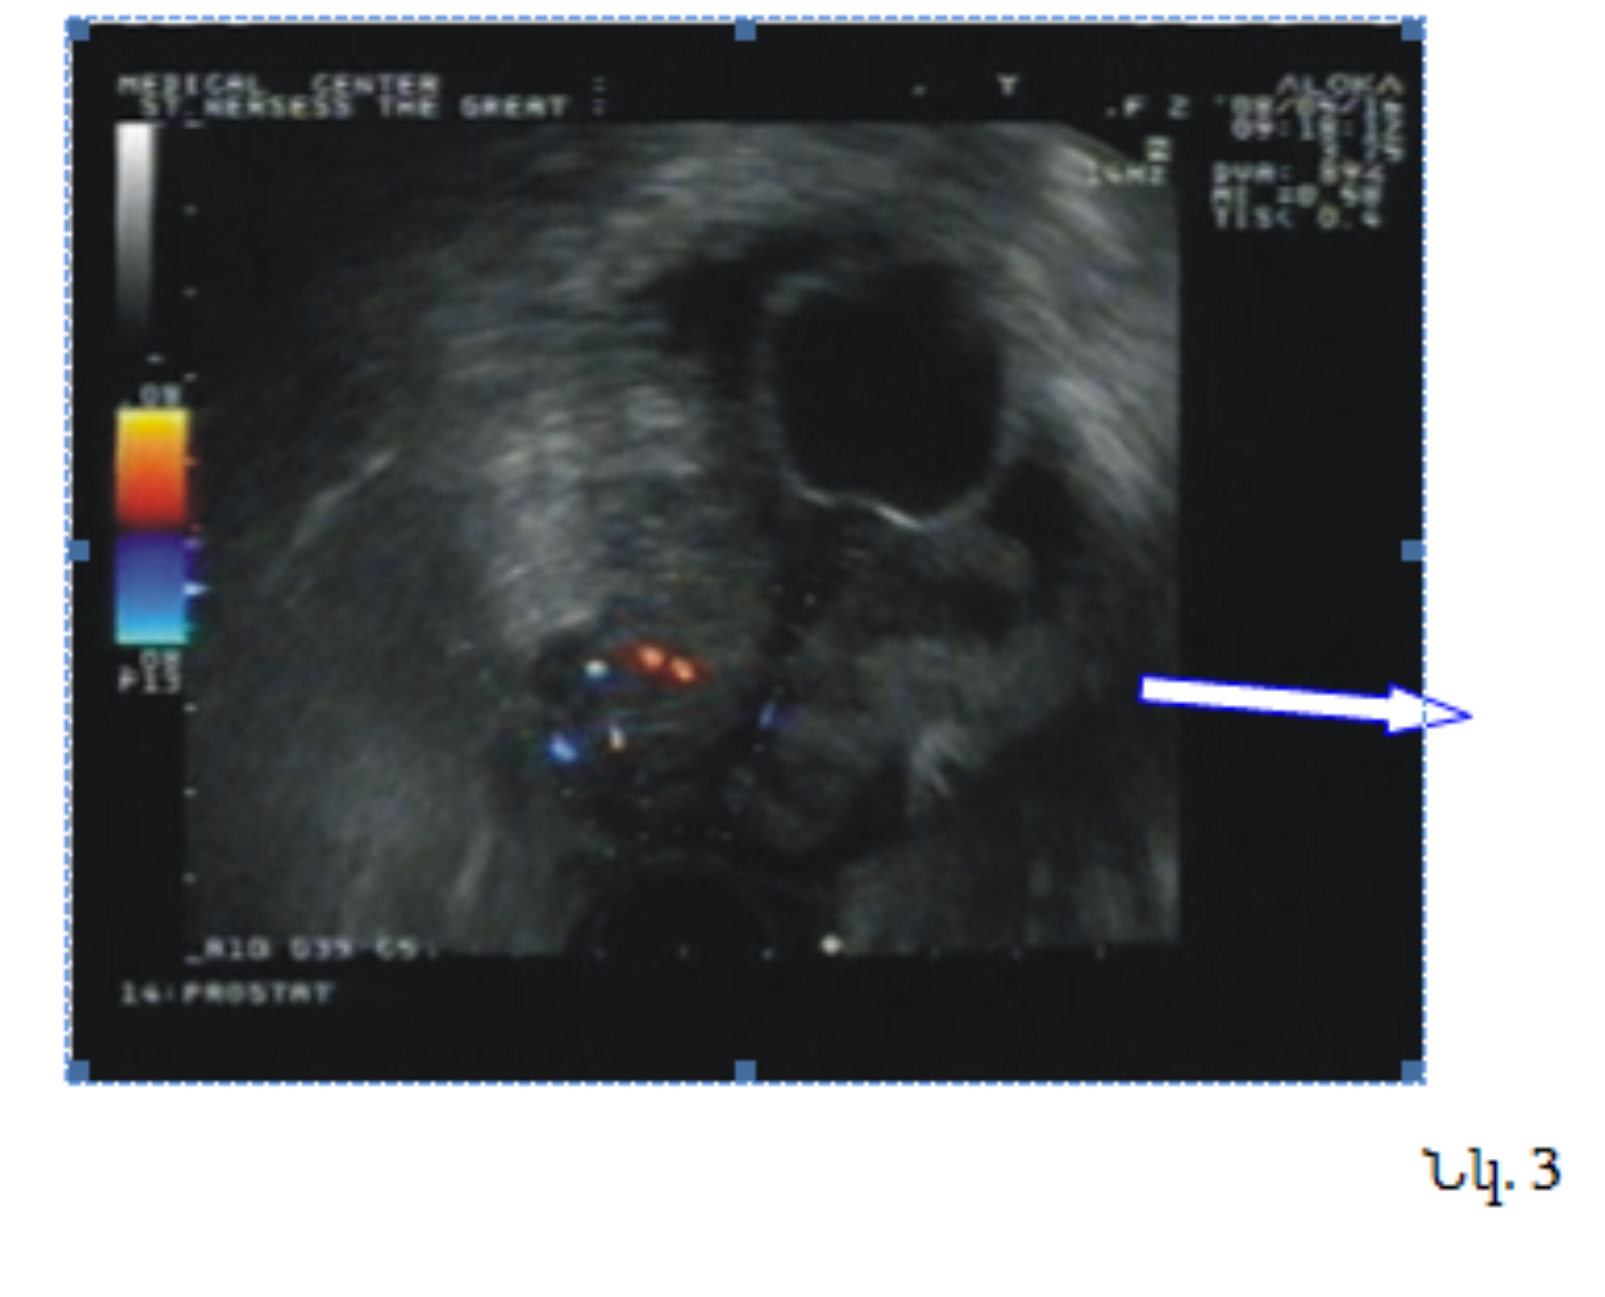

Վերջում ցանկանում ենք ներկայացնել մեր կատարած հետազոտություններից մեկ դեպք, երբ գորշ սանդղակով շագանակագեղձի տրանսռեկտալ ուլտրաձայնային հետազոտության ժամանակ աջ բլթում հայտնաբերվել է հիպոէխոգեն գոյացություն (նկ. 1, դեղին սլաք), որի բիոպսիայից հյուսվածքային կտոր չի ստացվել (հավանաբար կիստոզ գոյացություն է): Սակայն հարակից զոնայից, որը էներգետիկ (նկ. 2) և գունավոր (նկ. 3) ռեժիմներով հիպերվասկուլյար օջախ է, իսկ գորշ սանդղակով` իզոէխոգեն-ստացվել է շագանակագեղձի ադենոկարցինոմա Գլիսոն 3+3=6 բալ: